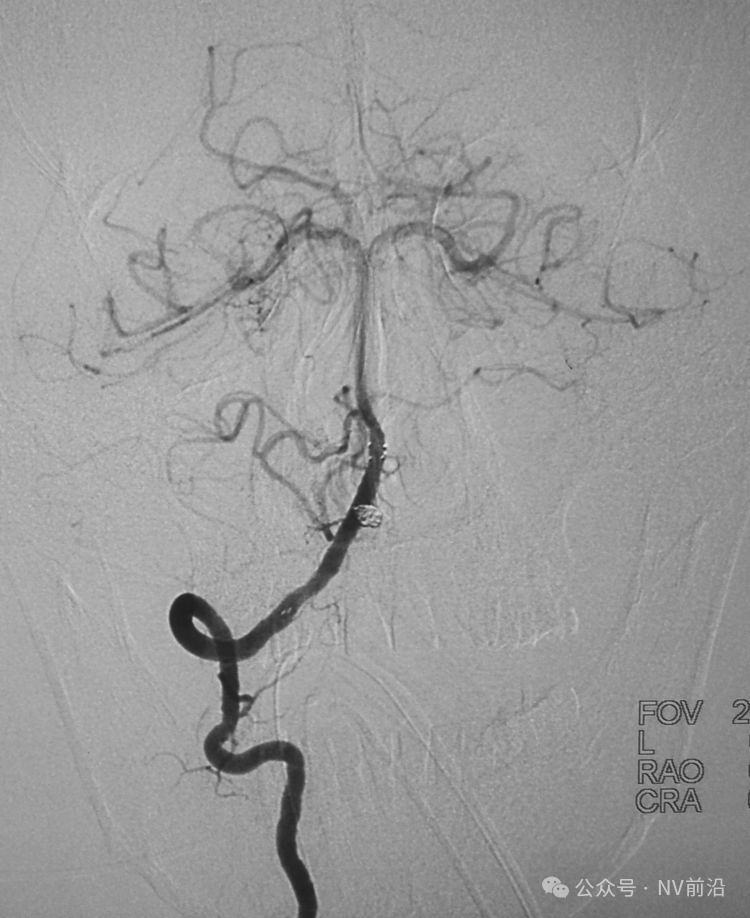

术后左颈内动脉工作位造影和蒙片。

术后左颈内动脉造影三维重建显示动脉瘤消失。